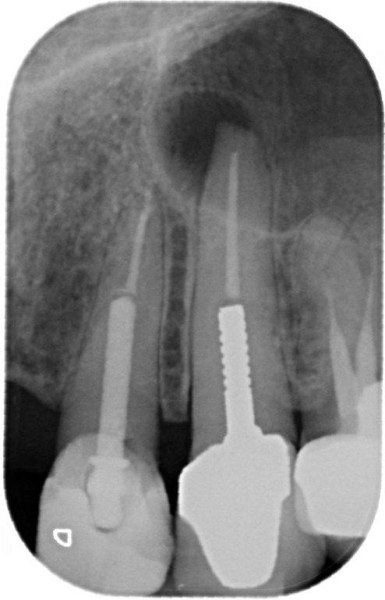

Post removal cases